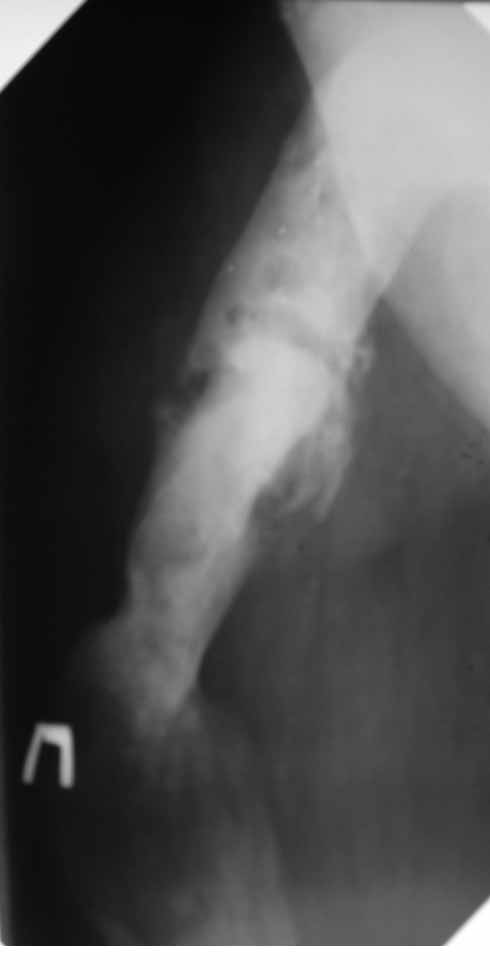

В анамнезе этапные операции по поводу устранения Coxa Vara, формирование артродеза коленного сустава, удлинения бедра. В данный момент беспокоит укорочение 7 см, эквинус стопы. Объективно: - местный статус виден на фото, сосудистых и неврологических расстройств нет. Обратился в консультативном порядке, настроен на удлинение голени в г.Волгограде. (со слов больного - не берут без санации очага на голени). Ваши предложения? Из кулуарных соображений - а не актиномикоз ли это? Иссечение рубцов+ VAC+ Стержень с аппаратом + микрососудистый трансплантат(?)

Ваш вопрос, коллега, вполне правомерен. В советское время те из нас, кто занимался костно-гнойной инфекцией видели достаточное количество подобных несчастных, кочующих из стационара в стационар. Своеобразный госпитализм приводил к тому, что люди тратили всю свою, как правило достаточно короткую жизнь, на лечение зачастую реально неизлечимых процессов. В данном случае имеющаяся рентгенологическая картина груботрабекулярной перестройки кости, сочетающаяся с участками склероза говорит, скорее всего, о том, что вся имеющаяся картина, дополненная чудесными фотографиями,вполне укладывается в клинику гематогенного остеомиелита, которым и страдает пациент с детства. Никакие санации, к сожалению, не приведут в данном случае к излечению, так как все имеющиеся рубцы являются зоной жизни этой самой инфекции. При продолжении лечения не исключено достаточно раннее развитие амилоидоза в этом случае. Мне кажется, что оптимальным было бы определить пациента в институт протезирования и протезостроения или в то учреждение, которое в регионе выполняет данную функцию. Специалисты помогли бы определиться с уровнем ампутации, являющейся, по сути, единственным способом разорвть порочный круг и дать пациенту возможность какой-то социальной адаптации. А в плановом порядке, насколько мне известно, можно добиться неплохого финансового обеспечения под протез конечности по квоте. Другого решения здесь нет. С уважением, Андрей Волна

извините за очепятку - не берут без санации очага на бедре. Сейчас имеется отделяемое из нижнего свища с периодическим выходом секвестром в виде мелкой крошки. Движений в ТБС почти нет - есть только сгибание градусов до 10. В стопе - только качательные.

Чтобы пытаться провести лечение данного пациента надо точно понимать - что хочет пациент? Какими усилиями с его и врачей стороны? В какой временной промежуток?. Предложение Андрея Волны возможно, если пациент уже ничего не хочет, или не возможно ему помочь по причине органной недостаточности - амилоидоз. Тогда, конечно, ампутация, протезирование. Возможно, на западе в том числе по экономическим причинам так и поступают. Но судя по литературе далеко не всегда. Эта тактика напоминает известное выражение "Есть человек, есть проблемы,..." ну и так далее. Если пытаться помочь пациенту, то гематогенный остеомиелит не настолько неразрешимая проблема. Хотя не понятно, почему удлинение за счет голени, при ложном суставе бедра. Я бы начал с попытки сращения бедренной кости, любыми возможными на взгляд лечащего хирурга методами (возможно придется их менять по ходу лечения или комбинировать). При мелких секвестрах удаление оных, но в первую очередь создать опорную конечность. Вторым этапом. Купирование гнойного процесса в тех очагах где он остался. При этом, кроме стандартных остеонекрэктомий с дренированием, можно и с VAC (мода вещь великая, а, может, и реально помогает, своего опыта, к сожалению, в применении современного VAC не имею, хотя, мне кажется, в основе это давно известные методы, изложенные у М.Кузина в "Гнойной хирургии"), кроме стандартных остеонекрэктомий необходима пересадка большого сальника в область гематогенного гнойного процесса. Пересадку можно сделать как свободным лоскутом, так и возвожна раскройка его в длинный кровоснабжаемый лоскут и с протягиванием под паховой складкой и распластыванием в зонах гнойных очагов бедра и голени. При наличии организационно нескольких бригад хирургов и подготовленных анестезиологов можно совместить оба этапа (операция может занять до 16 часов). Пересадка большого сальника в зону гематогенного гнойного очага в кости практически дает выздоровление или стойкую ремиссию ( проверено на полифокальных и монофокальных гематогенных остеомиелитах). Далее удлинять конечность в каком угодно месте, но я бы стал делать дистальнее, тем более что это может потребовать, во-первых, неоднократных остеотомий, во вторых, имеется потерянная иннервация малоберцовым нервом (говорится об укорочении 7 см и об эквинусе), и можно совместить удлинение с решением проблемы эквинуса. Это общий план. Надо принять во внимание, что по моему опыту это может потребовать до 8 лет перманентного оперативного лечения в худшем случае. Не все пациенты и врачи готовы к такому марафону. Но опять же по моему опыту, пересадка сальника в зону гематогенного патологического очага давала стойкую ремиссию. У меня был один пациент который после пересадки сальника через 3 года сломал голень с гематогенным очагом - криминальная травма- но гематогенный остеомиелит не обострился, а перелом голени срастался в обычные сроки в гипсе (4-6 мес). Но вернуться к теме ампутации можно на любом этапе. Кстати, надо будет при этом понять на каком уровне ампутировать. Ну и конечно, надо помнить о болезнях культей, в нашем случае это очень возможно (в Новокузнецком институте протезирования было даже отделение болезней культей, в том числе и гнойных). Это как в эндопротезировании суставов - решаем одну проблему, но можем получить другую. С уважением Ангельский А.А.